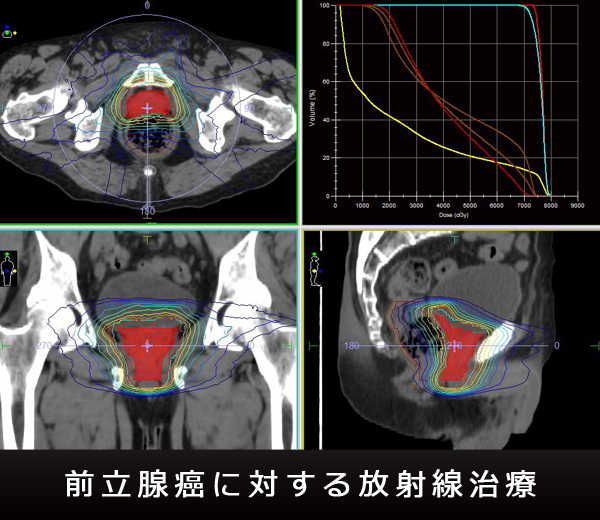

昔は、放射線治療というと、末期がんだけに行われる治療だとか、皮膚障害など副作用が怖いといった印象を持つ人が多かったようです。しかしながら、現代の放射線治療では、高線量の放射線をがんの存在する部位に集中させ、周囲の正常臓器の線量を大幅に抑制することが可能になっています。がんには濃く、正常組織には薄くという、精密な線量の塗り分けこそが、現在の放射線治療の真髄です。定位放射線治療 (SRT)、強度変調放射線治療 (IMRT)、画像誘導放射線照射 (IGRT) などの高精度照射技術の進歩と普及により、「がんに厳しく、身体に優しい」という放射線治療の特徴は、様々な臓器のがん治療に活用されています。

- 治療計画CT:実際の治療開始の1日~2週間前に、放射線治療部門内にある専用装置にて、治療計画CTを撮影します。撮影には数十分かかります。外来初診日同日に撮影する場合と、後日改めて撮影に来ていただく場合があります。CT撮影と同時に、頭部固定用マスクを作成したり、皮膚に位置確認のマークを付けたりします。このCT撮影は、治療計画のために行うものです。放射線照射の角度、照射範囲、強さのバランスなどを、患者さんの体型や、腫瘍の場所、広がり、性質にもとづいて精密にデザインし、個々の患者さんごとに放射線照射の設計図を作成します。